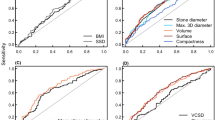

The correlation with and influence of a range of baseline characteristics on treatment outcome of SWL was examined: patient’s age, gender, weight, and BMI; stone location and volume, MAV, SSD; use of alpha blockers; presence of ureteral stents. Both univariate (chi-square or Mann–Whitney U-tests for dichotomous or continuous variables) and multivariate (binary logistic regression) analyses were performed to define significant factors. ROC curves were used for the determination of the best cut-off values. All tests were two-sided and a p-value of <0.05 was necessary to reject the null-hypothesis. Statistical analyses were performed using IBM SPSS Statistics Version 22 (IBM Corp., New York, U.S.A.).

The ROC curves for different parameters were analyzed to find the optimum cut-off values to predict disintegration failure (Fig. 3). The optimum cut-off point for SSD (90°) would be >11.9 cm (sensitivity 65.4 %, specificity 65.3 %), for patient weight >82.5 kg (sensitivity 65.4 %, specificity 71.4 %), and for BMI >25.9 kg/m2 (sensitivity 69.2 %, specifity 55.1 %).